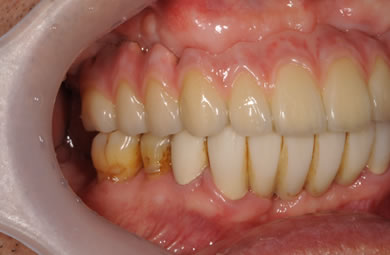

骨再生スピードインプラント治療+AGC連結セラミック治療+セラミック治療

| 治療方針 | ソケットリフト法により上顎洞底部を拳上することにより、骨の無い部分に骨をつくってあげ、インプラント治療を可能にする。さらに歯周病により組織の破壊が著しいので、AGC連結セラミック治療により上顎の審美的回復を行う。 | ||||||||||||||||||||||||||||||||

| 治療内容 | インプラント7本(抜歯AGC即日スピードインプラント+ソケットリフト)、AGCハイブリッドセラミック連結ブリッジ1装置(上顎)ハイブリッドセラミック8本 | ||||||||||||||||||||||||||||||||